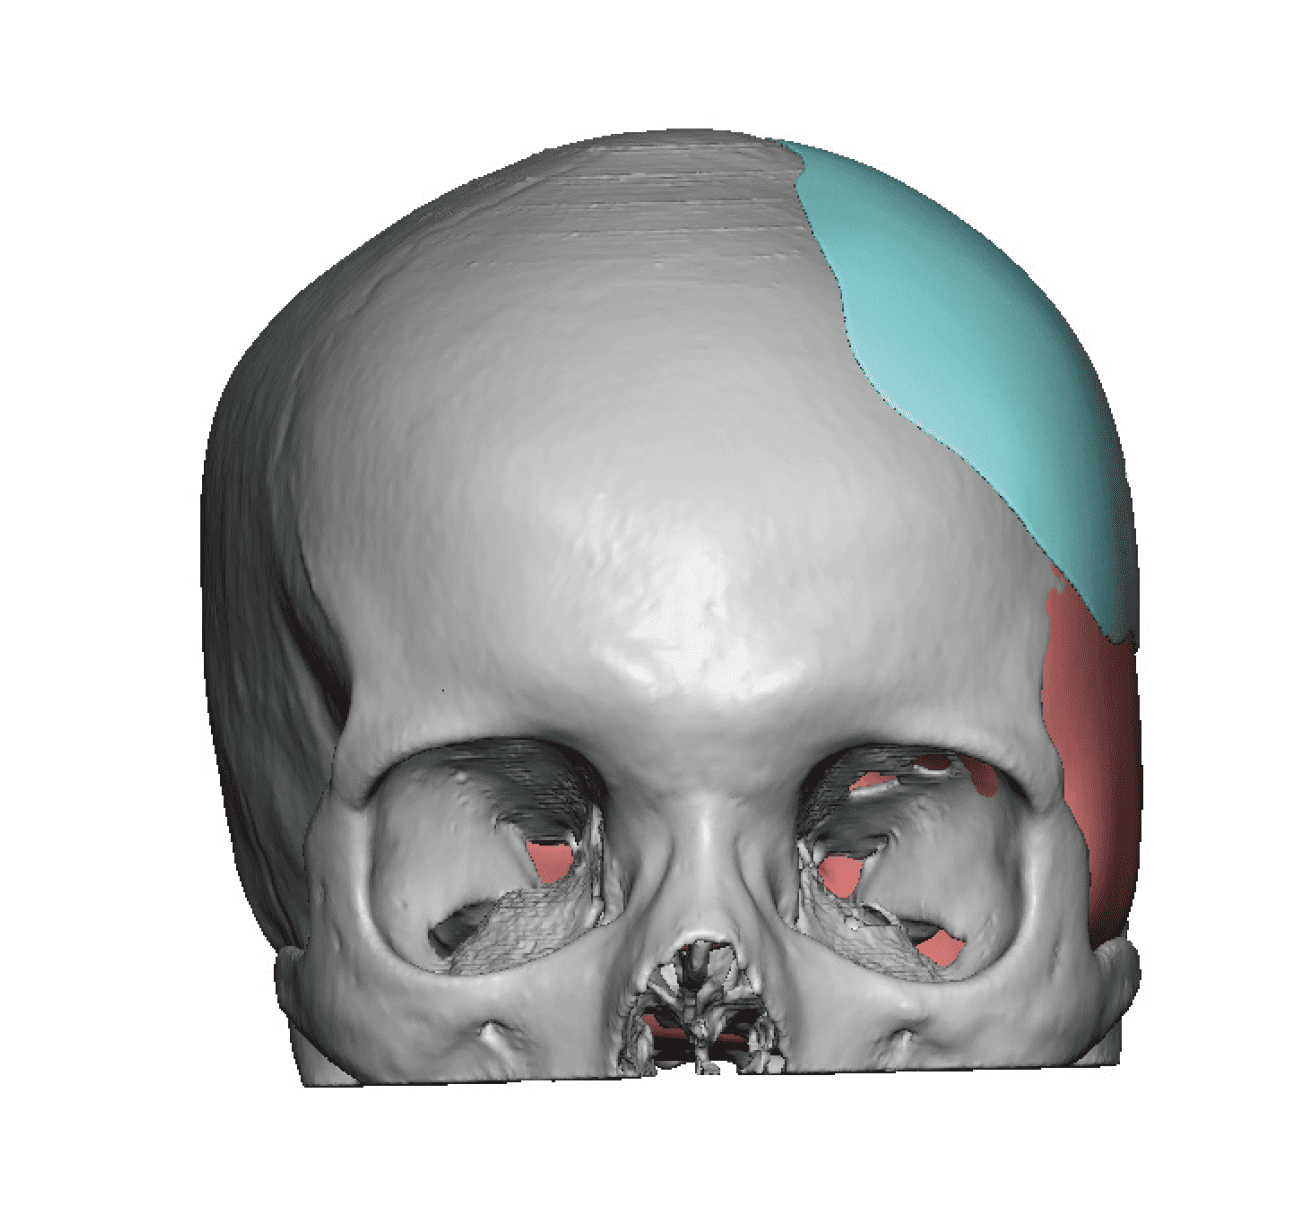

Patient 84

Desire for change of head shape from front view form an inverted V shape to a rounder and wider head shape.

Placement of custom extended forehead-temporal implants through incisions in the crease behind the ear. (he had a prior back of head skull implant which is green in the implant designs and which the head widening implants partially covered it)

Desire for change of head shape from front view form an inverted V shape to a rounder and wider head shape.

Placement of custom extended forehead-temporal implants through incisions in the crease behind the ear. (he had a prior back of head skull implant which is green in the implant designs and which the head widening implants partially covered it)